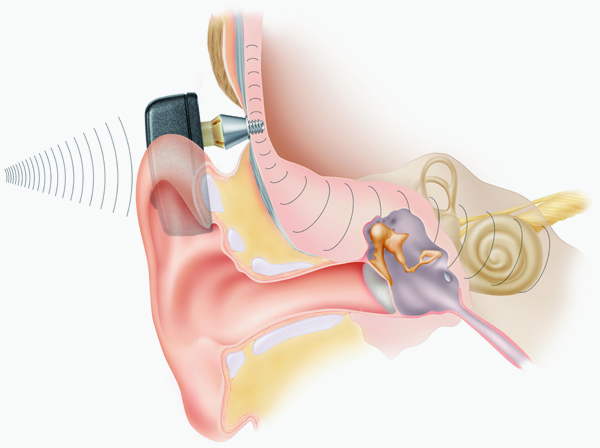

Современные слуховые аппараты при сенсоневральной тугоухости